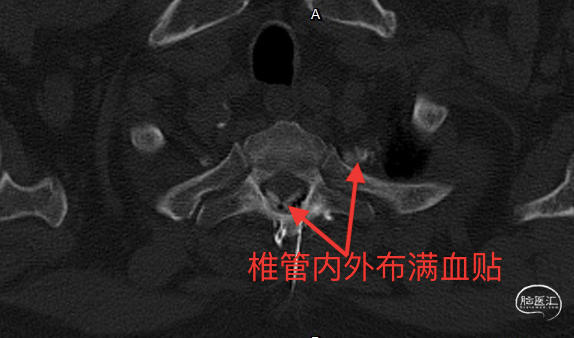

至此,漏点明确,行T1-2非常规靶向血贴治疗,用血10+ml。

术后CT如上,按常规只需要卧床24小时,其后下床活动,患者即感头晕症状明显改善,术后5天出院,头晕、头沉症状完全消失,困扰患者两年的顽疾痊愈了。